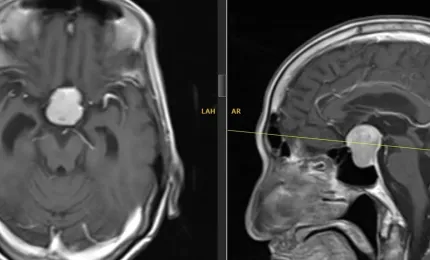

Nỗ lực giành sự sống của bệnh nhân ung thư gan giai đoạn cuối

Ung thư gan giai đoạn cuối kèm theo hàng loạt biến chứng như tắc mật, nhiễm trùng huyết, nhiễm nấm phổi, suy đa cơ qu